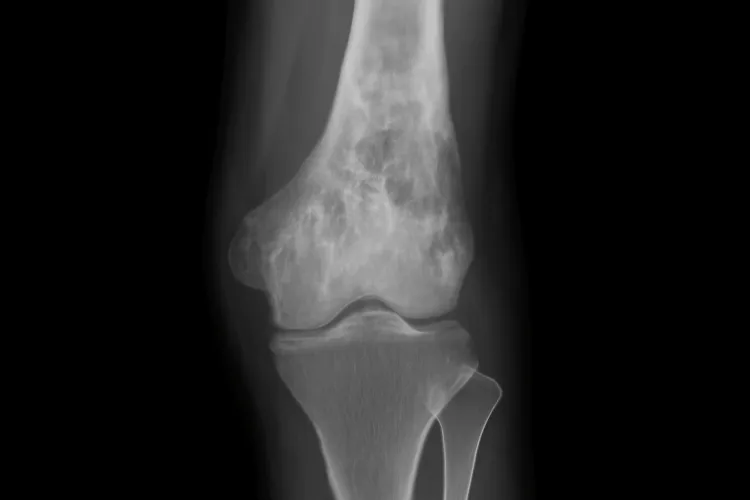

Одним из ключевых методов диагностики является МРТ, который позволяет получить детальное изображение костной ткани и прилежащих структур. Этот метод помогает выявить воспалительные изменения на ранних стадиях, а также уточнить степень повреждения. Кроме того, для диагностики могут использоваться рентгенографические исследования, которые помогают обнаружить возможные изменения в костях, характерные для остеомиелита.